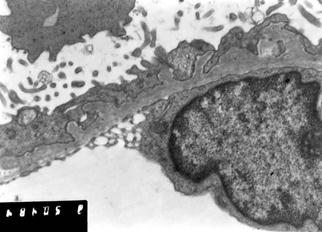

Патоморфология. Гистологические изменения при МН свидетельствуют о главенствующей роли иммунных комплексов, расположенных субэпителиально (между ГБМ и подоцитами). Субэпителиальные (эпимембранозные) иммунные депозиты не приводят к воспалению или привлечению циркулирующих лейкоцитов (нефрит), а в большей степени вызывает комплемент-зависимое повреждение подоцитов и нефротический синдром. Таким образом, при МН происходит утолщение ГБМ без пролиферации клеток. Различаются четыре стадии эволюции МН: стадия I с мелкими субэпителиальными депозитами (светло-серые), стадия II с шипиками, стадия III с новообразованной ГБМ вокруг депозитов и стадия IV с неравномерным утолщением ГБМ и растворением депозитов. (рис.8)

Во II стадии ГБМ иммунные депозиты увеличиваются, ГБМ слегка утолщена. Окраска серебром выявляет типичные шипики — выросты с наружной поверхности ГБМ. Подоцит образует новый материал для ГБМ.

В III стадии белковые (электронно-плотные) депозиты полностью покрываются новообразованной ГБМ и полностью располагаются внутри нее. Вся ГБМ заметно утолщена.

В IV стадии толщина ГБМ становится крайне неравномерной из-за резорбции протеиновых депозитов, на месте которых остаются пустоты (хорошо видимые на ЭМ). В стадиях III в IV обнаруживается все больше и больше полностью или сегментарно склерозированных клубочков.

Рис.8 Мембранозная нефропатия (I-IV стадии) (C.Jenett, 1995)

A. Схема развития мембранозной нефропатии I. В более поздних стадиях базальная мембрана покрывается субэпителиальными шипиками; II. ЭМ демонстрирует новообразованную ГБМ между электронно-плотными депозитами; III. В еще более поздних стадиях ГБМ приобретает двойной контур: протеиновые депозиты покрыты новообразованной ГБМ (III стадия); IV. ЭМ теперь показывает плотные депозиты в разных стадиях разрешения. Местами остаются почти пустые отверстия (IV стадия).

С. II стадия мембранозной нефропатии: отчетливые субэпителиальные шипы ГБМ, слияние ножек и микровиллезная трансформация подоцитов. Электронная микроскопия.